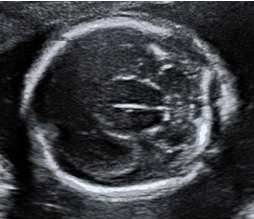

28歲孕婦,G2P1,妊娠16週,接受超音波檢查如圖所示,下列何者為最可能的診斷?